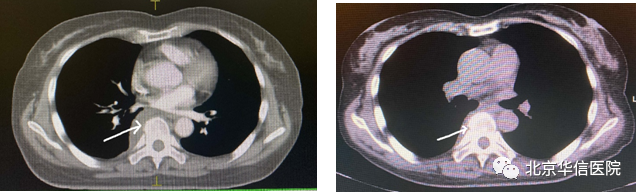

右侧脊柱旁放疗前后对比图,见箭头所示(左图为放疗前)